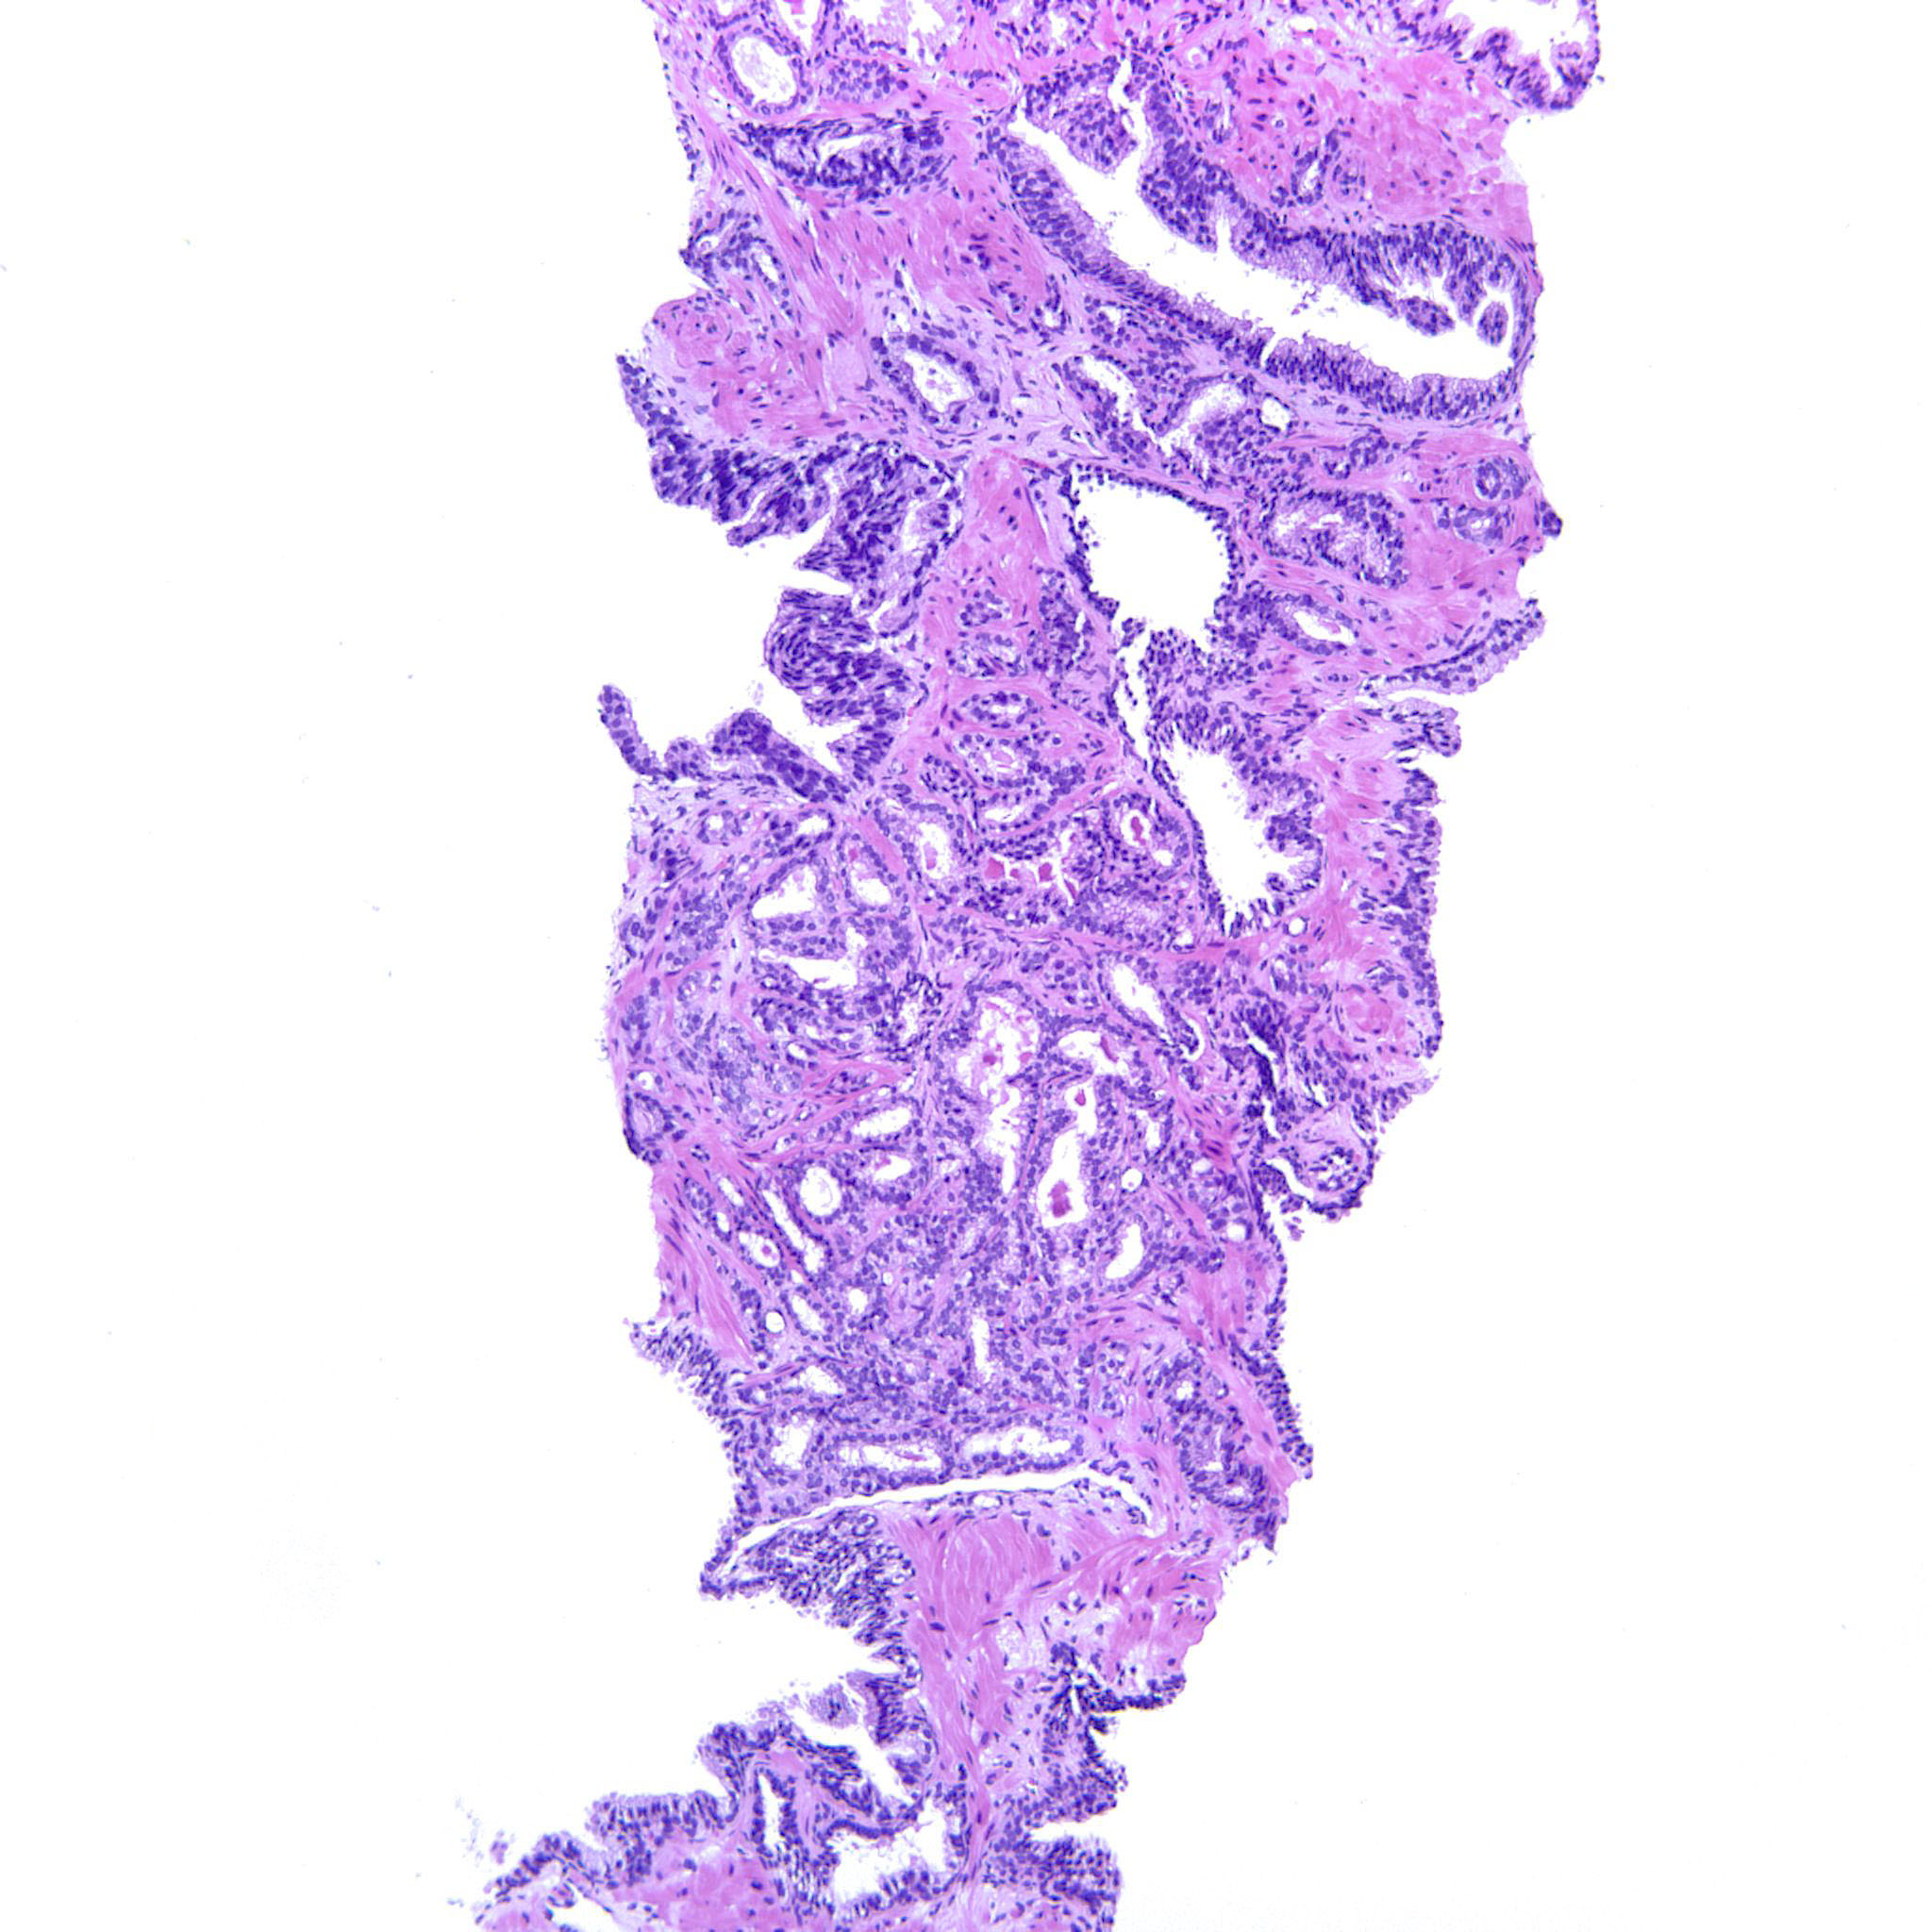

Prostate cancer grading

Case ID: 752